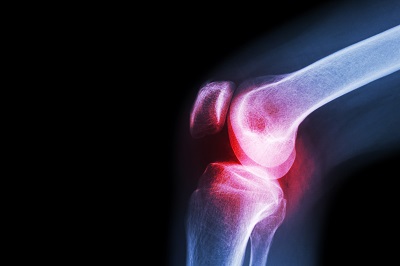

消除痛风的3个好办法 盘点缓解痛风的妙招:痛风是一种关节方面的疾病,主要是因为体内的尿酸没能正常排出造成的,而痛风是有发作期的,一旦发作时,很多患者都无法忍受疼痛,所以很

痛风是一种关节方面的疾病,主要是因为体内的尿酸没能正常排出造成的,而痛风是有发作期的,一旦发作时,很多患者都无法忍受疼痛,所以很多患者都会选择服用药物来解决,但在除了服药外,如果采取相应的措施,也是可以缓解疼痛的,下面就来看看,消除痛风的3个好办法是什么吧。